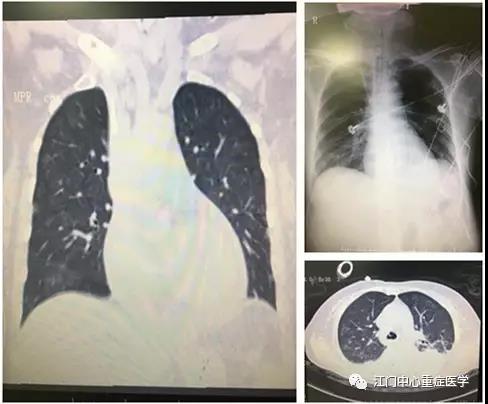

转入ICU后,经过重症医学科医生的详细查体发现,何婆婆除了全身散发红色点状皮疹之外,在左侧腹股沟处暗藏一个不显眼的焦痂,周围泛着红晕。根据多年的临床经验,结合婆婆血小板明显减少、胸部CT提示双肺广泛渗出以及多浆膜腔积液等检查结果,当班医生认为“恙虫病”的可能性极大,它引起了全身小血管炎,由于肺部血供极为丰富,极易受累。组织病情讨论后,决定使用呼吸机支持肺脏,还采用强力抗感染联合多器官支持。

虽然诊断明确了,但何婆婆病情仍不乐观,上呼吸机辅助呼吸后,血氧有所改善,可血压持续偏低,难以满足全身器官的需求。主管医疗小组经讨论后考虑,除了肺部受累,婆婆的心脏功能也可能受损,应迅速完善心脏彩超、PiCCO等检查及监测。